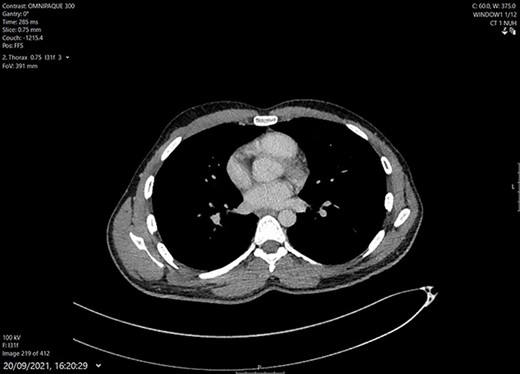

The PCR and histology results were both positive for TB. Cultures grew a fully sensitive Mycobacterium tuberculosis bacilli. He was seen in ID clinic and commenced on antitubercular treatment. Initially, he had 2-month intensive therapy of Rifampin, Isoniazid, Ethambutol and Pyrazinamide. The Pyrazinamide was stopped at 6 weeks due to issues with arthralgia. For maintenance therapy he continued for a total 7 months of Rifampin and Isoniazid due to the short course of Pyrazinamide. He had a repeat CT thorax after completing treatment, which showed resolution of the abscess and infection with no evidence of osteomyelitis (Fig. 3).

CT Thorax after completing 9 months of medical treatment and surgical debridement of abscess. Shows complete resolution of chest wall mass and intact bony structure underneath.